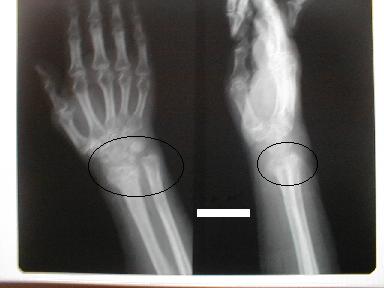

1月23日整復固定 正面像

側面像

2月3日正面像